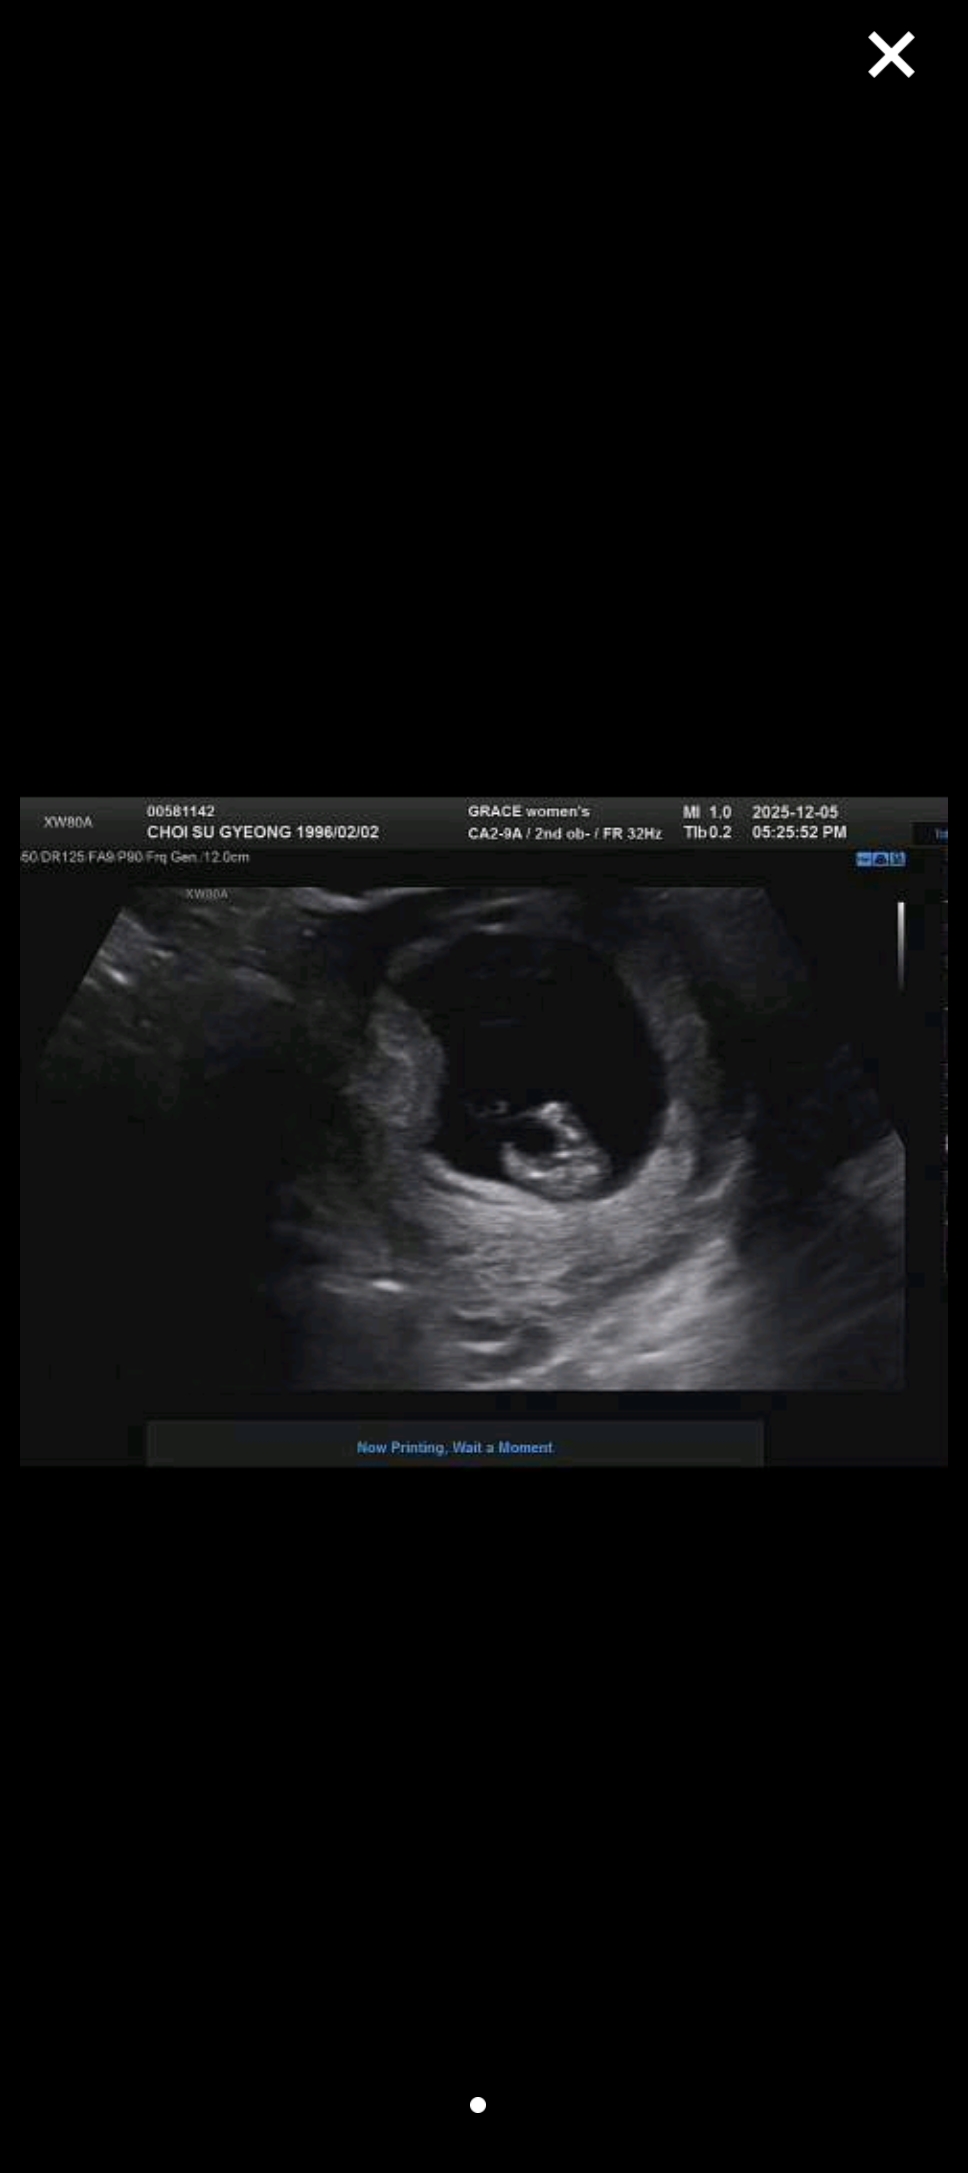

10주 좀 넘어서 좀 이르긴 하지만 아들일까요 딸일까요

선생님은 조심스럽게 가랑이가 깨끗하다고(?) 딸 일거 같다고 하시는데, 어떻게 보이시나요~??